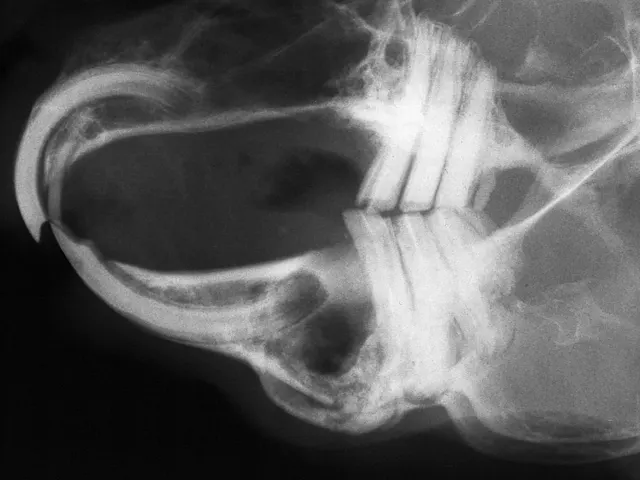

Owners should be prepared for the typically unattractive postoperative appearance of marsupialization of soft tissues (A). The postoperative radiograph shows a wide radiolucent area corresponding to the debrided bone site, and the tooth fragment is no longer visible (B).